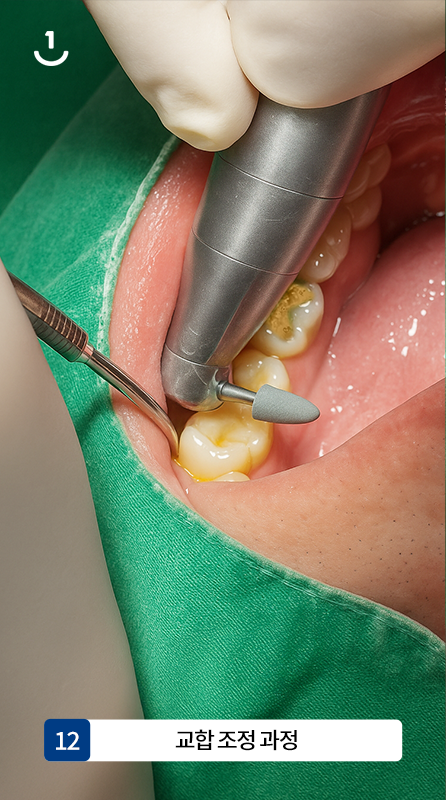

12

교합 조정 과정